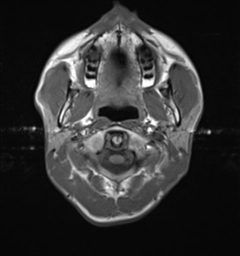

Khí hóa bất đối xứng đỉnh xương đá (Asymmetric pneumatization of the petrous apex)